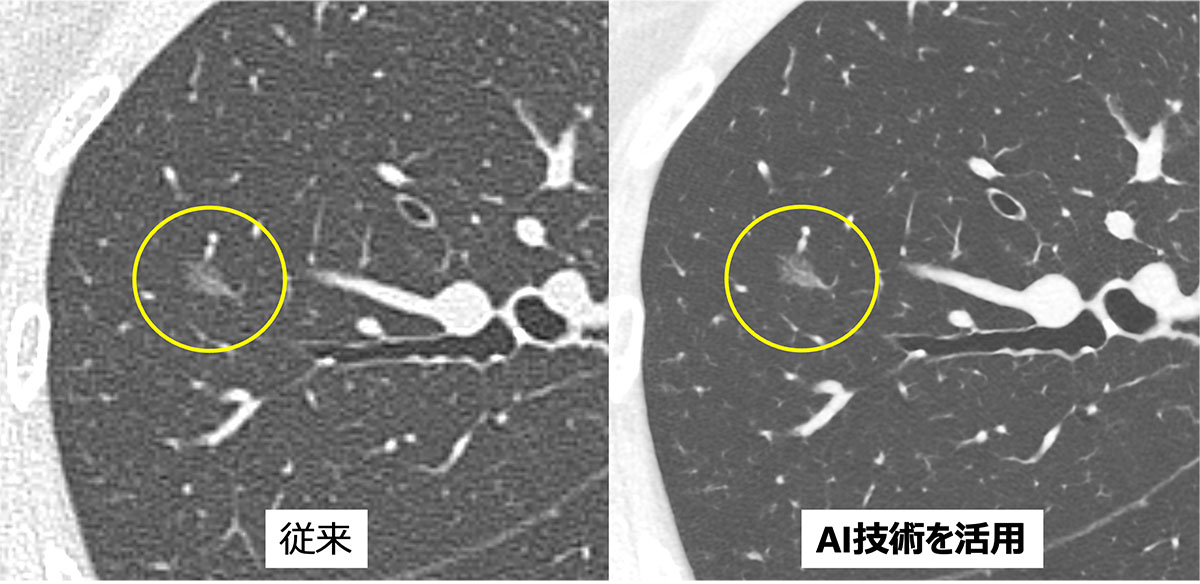

人工知能(AI)技術と特殊機能

新たなAI技術と特殊機能が多く備わりました。すべてのCT検査に対してAI技術を活用してCT画像の大幅な画質の向上につなげています。さらに画像が劣化する原因となるもの(金属・動き)に対して特殊機能を活用することで、結果の精度と信頼性の向上が期待できます。

肺病変の従来画像(左)とAI技術を活用した画像(右)の比較。

AI技術を活用することで病変や肺の微小な構造が明瞭となっている。